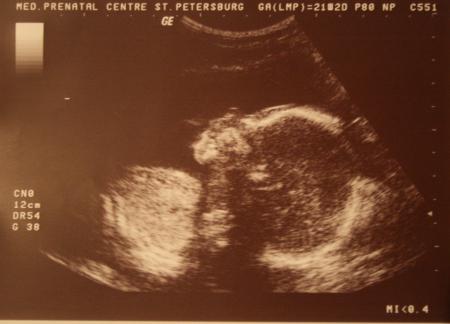

Узнали, что будет мальчик, было очень явно видно,счастью нет предела!!!! Вес уже 468 гр., а рост 29 см.У меня такие эмоции, даже не передать!!!!!

Сыночек в профиль (голова и плечи).